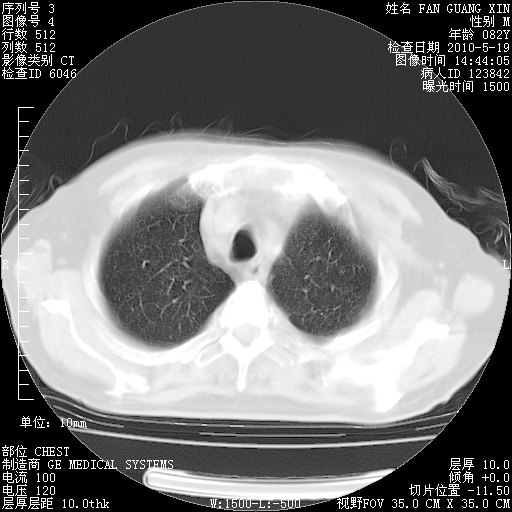

复查肺部CT,明显好转。为什么发热呢?

治疗3周后的肺部CT